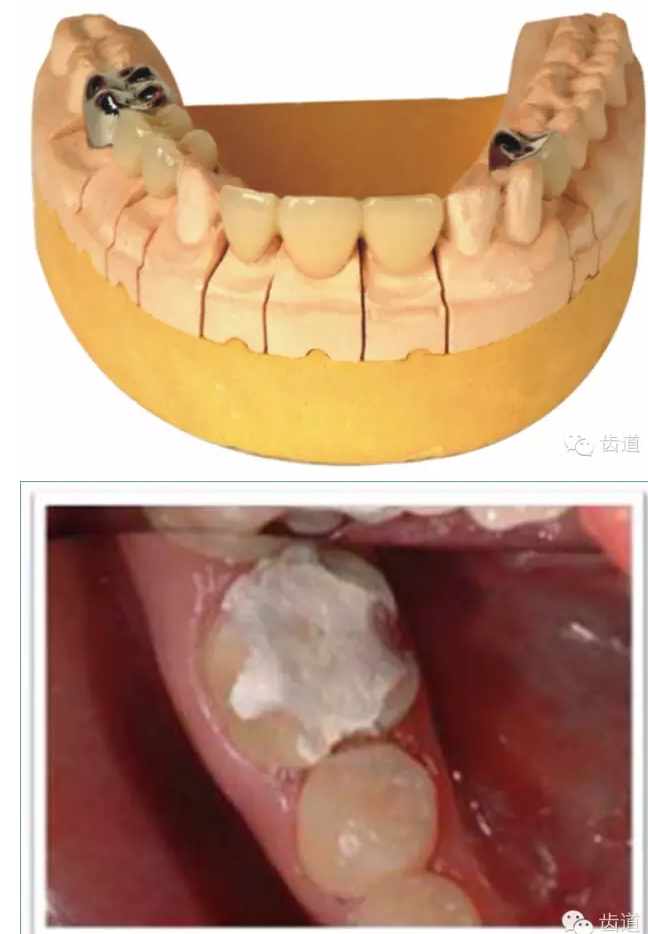

l多個(gè)基牙時(shí)就位道的調(diào)節(jié)

正壓力:即修復(fù)體的密貼程度(小于0.2mm)

表面粗糙程度

牙的外形及洞形的幾何形狀:主要是牙體制備出一定聚合角度產(chǎn)生的阻擋作用